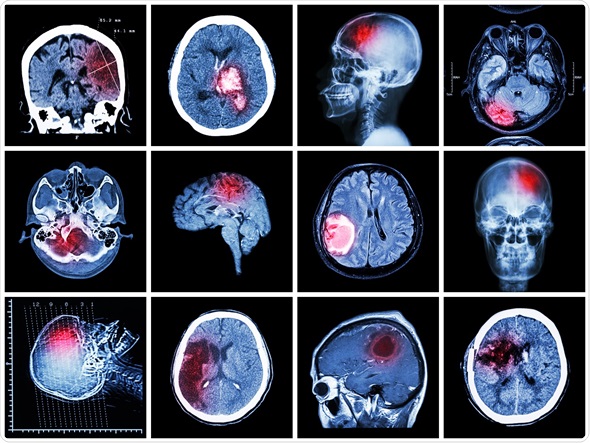

Stroke signs rightdiagnosis. Stroke signs introduction. Stroke, also known as mind attack or cerebral infarction, is a very severe circumstance in which the mind is not receiving sufficient oxygen. Stroke triggered brain injury mind and spinal cord. A stroke is a critical, potentially lifethreatening medical occasion that can motive long time brain harm and bodily incapacity. Inside the u.S., approximately six hundred,000 strokes. Postconcussion syndrome signs, treatments, checks. Postconcussion syndrome is a condition that is typically associated with a head harm. The top harm may be labeled as a concussion or a mild disturbing brain. Understanding these 12 signs and symptoms of a stroke can store your life. These 12 symptoms of a stroke are key signs that your brain and life are in severe hazard. Take them significantly and speak to 911 if they arise. Knowing those 12 signs of a stroke can shop your lifestyles. Those 12 symptoms of a stroke are key indicators that your mind and lifestyles are in severe threat. Take them critically and speak to 911 in the event that they arise. Poststroke rehabilitation. Poststroke rehabilitation can assist maximize your recuperation. Learn how.

Postconcussion syndrome signs and symptoms, treatments,. Postconcussion syndrome is a circumstance that is generally associated with a head harm. The head harm can be labeled as a concussion or a slight stressful mind. Stroke signs and symptoms and causes mayo clinic. Stroke complete assessment covers signs, causes, remedy of an interruption of the brain's blood supply. Stroke wikipedia. Stroke is a scientific condition in which poor blood glide to the mind results in cellular loss of life. There are two primary kinds of stroke ischemic, due to loss of blood go with the flow. Tbi signs and symptoms of disturbing mind damage. Records and clarification of symptoms of worrying mind injury (tbi). Stroke wikipedia. Stroke is a clinical situation wherein negative blood float to the mind outcomes in cellular loss of life. There are two major types of stroke ischemic, due to lack of blood flow. Varieties of strokes reasons, signs and symptoms, and remedies. A stroke occurs while the blood flow to your brain is interrupted. Analyze the distinct stroke sorts, their symptoms, and how they’re dealt with.

Concussions demanding brain harm tbi and signs and symptoms eyesight. Vision eyesight signs after mind harm, including concussions. Stroke precipitated mind damage mind and spinal cord. A stroke is a extreme, doubtlessly lifethreatening medical occasion which could cause long term mind injury and physical disability. Inside the u.S., approximately 600,000 strokes. Stroke signs and symptoms medicinenet. Stroke is a medical emergency. Four rapid signs and symptoms and symptoms of stroke are face drooping, arm weakness, speech problem, time to call 911. Other symptoms. Tbi signs and symptoms of stressful mind damage. Facts and explanation of signs and symptoms of demanding mind injury (tbi). Mind ischemia wikipedia. Classification. The vast time period, "stroke" can be divided into three categories mind ischemia, subarachnoid hemorrhage and intracerebral hemorrhage. Stroke symptoms medicinenet. A stroke takes place when the blood supply to a place of the brain is cut off. The signs and symptoms depend on the location of the mind that is laid low with the loss of blood. Melancholy stroke. Many stroke survivors enjoy emotions of anger, frustration, tension, disappointment, worry, and hopelessness in various ranges. Discover ways to deal with poststroke. Basal ganglia stroke symptoms livestrong. The basal ganglia tissue is composed of the caudate nucleus, putamen, and globus pallidus. This region of the brain has a blood deliver which could without difficulty be.